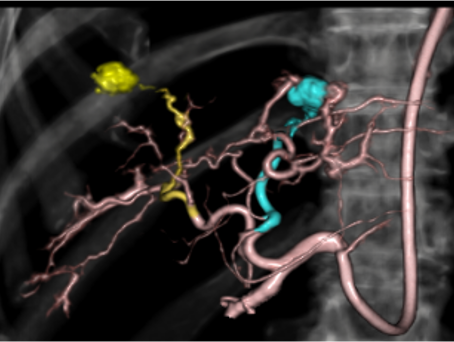

腫瘍を栄養している動脈や出血している動脈を塞栓物質で詰めて治療することです。当院で行っている冠動脈化学塞栓療法(TACE)は、がん細胞(腫瘍)に酸素や栄養素を供給している動脈を抗がん剤と塞栓物質で塞栓します。主にX線CT装置と一体になった血管造影装置(IVR-CT装置)で検査・治療を行いっており、 X線CT装置を使用して腫瘍の栄養血管を同定し、3D画像を作成することで、血管の走行や目的血管を立体的に描出し、手術支援を行っています。その他に、骨盤骨折や喀血などで出血している血管をコイルなどで詰めて止血します。

| 肝動脈DSA画像 | X線CT-3D画像 |